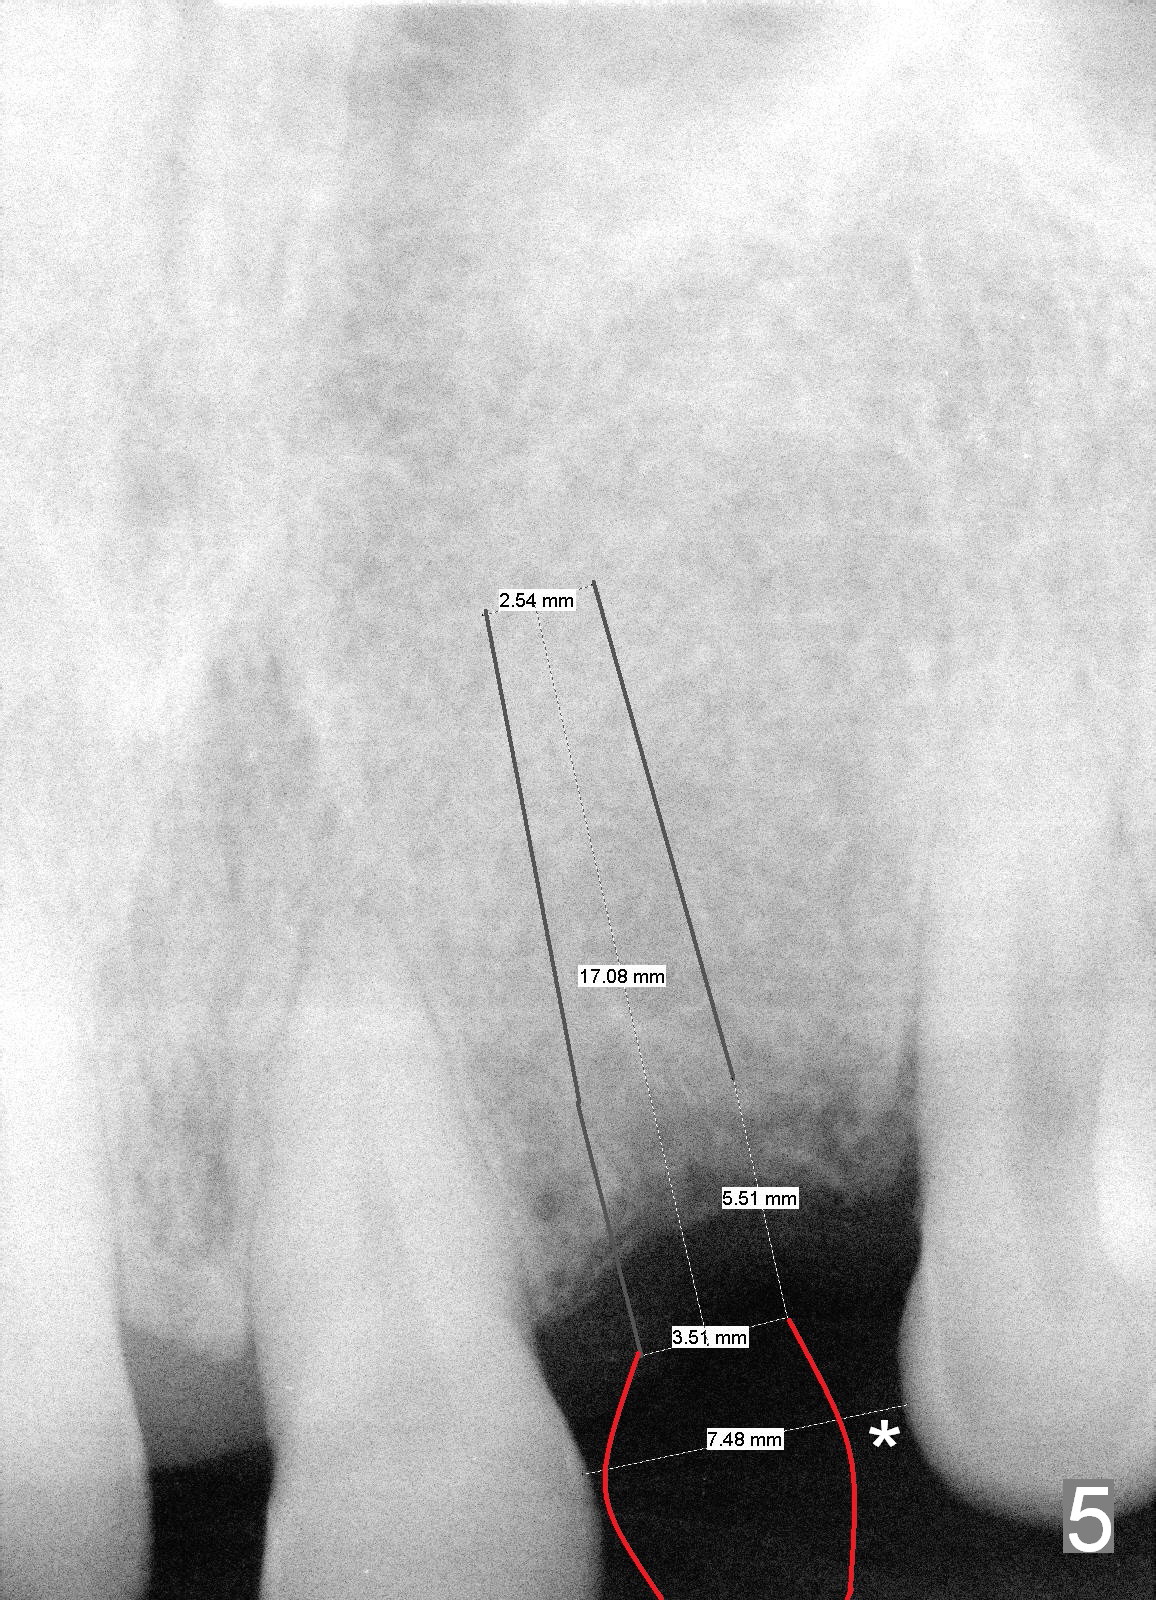

A 58-year-old man has multiple missing teeth including #14; the remaining teeth has sign of occlusal trauma (bone loss, Fig.1 arrowheads). The mesiodistal space of #14 is 8 mm (Fig.2). It appears that a 4.5x14 mm implant is appropriate for the site with sinus lift. Scalpel will be used to initiate osteotomy and bone expansion in case the bone density turns out to be low. To prevent the sinus membrane perforation, use a shorter implant (11 mm, Fig.3).